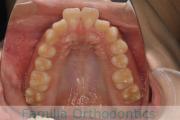

上顎

下顎